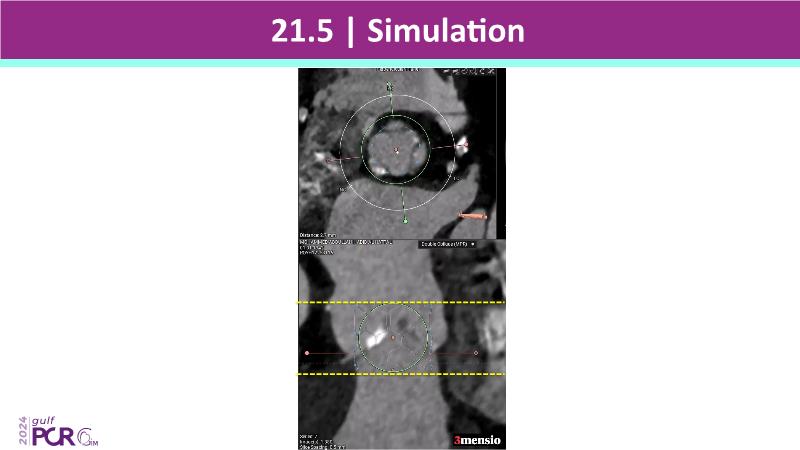

Stay ahead in TAVI innovation by exploring the advanced balloon-expandable Myval THV series. This session highlights the latest clinical data, optimal sizing and implantation techniques, and valuable real-world insights, including long-term follow-up results.

- To understand the best practices for Myval sizing and implantation technique for best outcomes